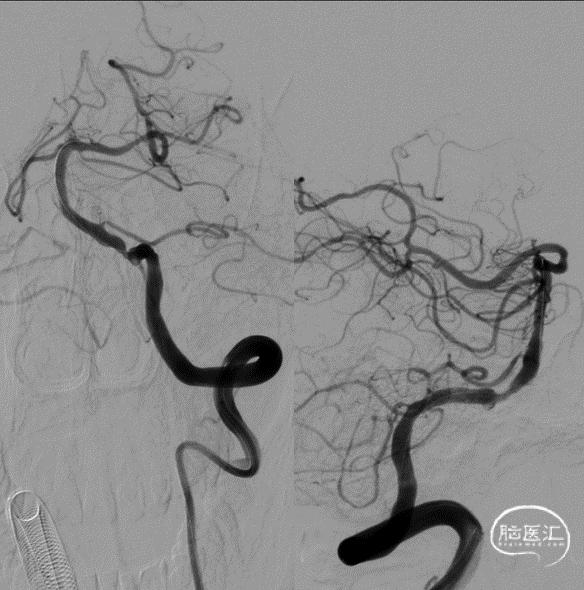

术后影像及检查

术中DynaCT。

术后4h CT。